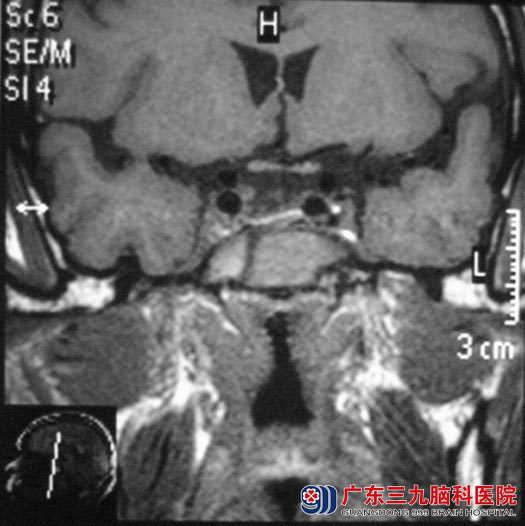

一年前韦先生出现头胀痛,一直未予重视,近日头痛加剧,当地头颅CT检查提示:鞍区占位,广东三九脑科医院头颅MR检查考虑垂体大腺瘤,大小约17.2mm×14mm×16.7mm。

5月28日,垂体瘤诊疗中心 鲁明主任主刀,在导航仪定位下,行经鼻蝶鞍区占位切除术,术前制定导航计划,术中再次导航定位,显微镜下见灰白色肿瘤,血供一般,质软,镜下切除肿瘤,修补鞍底,手术顺利。术后韦先生未出现脑脊液鼻漏、视力视野缺损、尿崩等术后并发症,已康复出院。术后病理结果为:垂体生长激素分泌腺瘤。